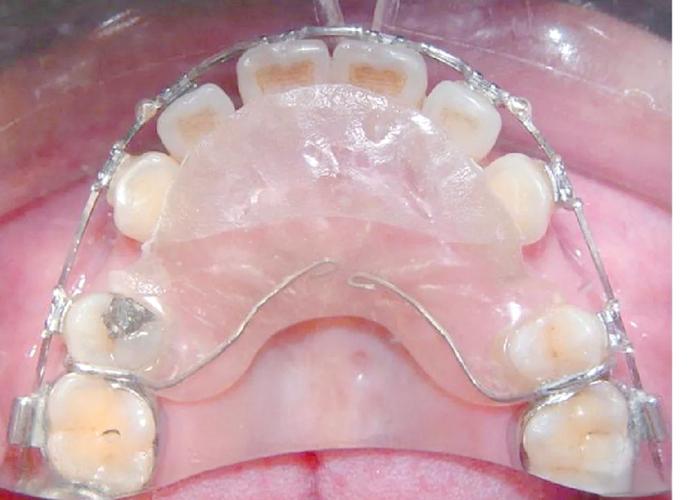

舌侧矫正器

- 特点: 将托槽和弓丝完全粘接在牙齿的舌侧面(靠舌头的那一面),从外面完全看不到。

舌侧矫正器图片,lingual braces before after,隐形牙套舌侧,inside braces - 优点: 真正意义上的隐形,美观性极佳。

- 缺点: 价格非常昂贵(通常是传统矫正的2-3倍或更高),初期发音和舌头适应困难,口腔清洁极其困难,对医生技术要求极高,复诊时间长。